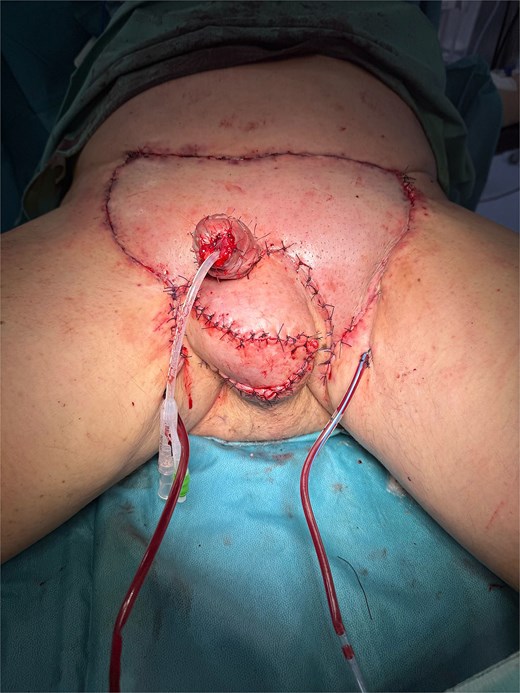

An en-bloc excision of all affected skin was performed, maintaining a minimum safety margin of 10 mm around each suspicious lesion (Fig. 3), exposing the testes and the spermatic cords, which were preserved. The scrotal dissection extended to the inguinal and perianal regions. The penile skin was incised dorsally in a book-like fashion down to the dartos fascia, then continued laterally and ventrally, with careful preservation of the urethra and its continuity with the scrotal skin. A glansectomy was then performed. Subsequently, the scrotum was reconstructed using double-opposing Singapore flaps, while penile reconstruction involved a lower abdominal Keystone flap for the base and a split-thickness skin graft for the shaft (Fig. 4).